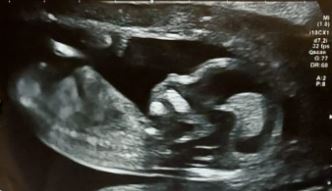

Přikládám fotku toho malého neposedy